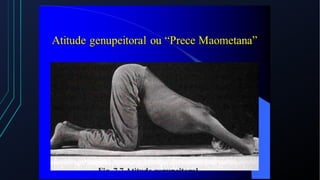

Dor torácica pode ter diversas causas, incluindo cardíacas como síndrome coronariana aguda, dissecção de aorta e pericardite, e não cardíacas como problemas pulmonares, musculoesqueléticos e do trato gastrointestinal. É importante avaliar a história clínica, características da dor e exame físico para identificar a possível causa e orientar o tratamento adequado.